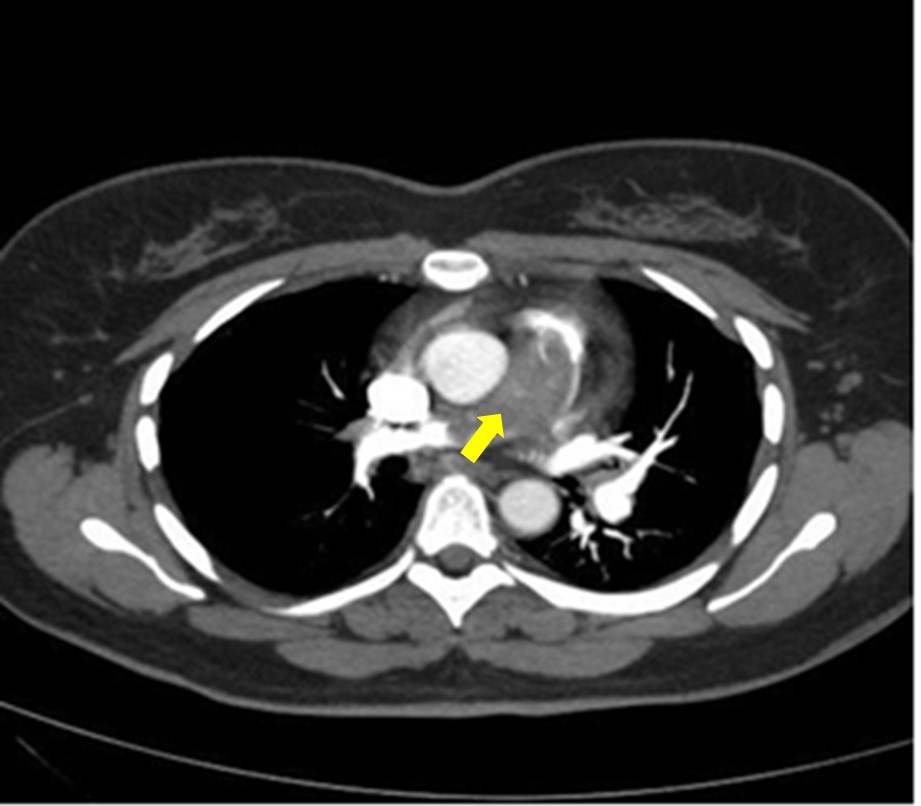

PE diagnosis was verified using the entire range of laboratory and instrumental diagnostic methods in accordance with the current clinical recommendations, the most informative method being multispectral computed tomography-angiopneumography (MSCT-APG) with contrast, by the results of which all the patients were diagnosed with the trunk form of PE, and the condition of the peripheral pulmonary arterial bed was evaluated, which is one of the most important prognostic clinical factors (Figure 1).

Fig. 1. Multispectral computed tomography-angiopneumography with contrast: central form of pulmonary embolism with location of the embolus in the trunk and the main branches of the pulmonary artery.

Note: the arrow indicates a thromboembolus in the trunk and bifurcation of the pulmonary artery.